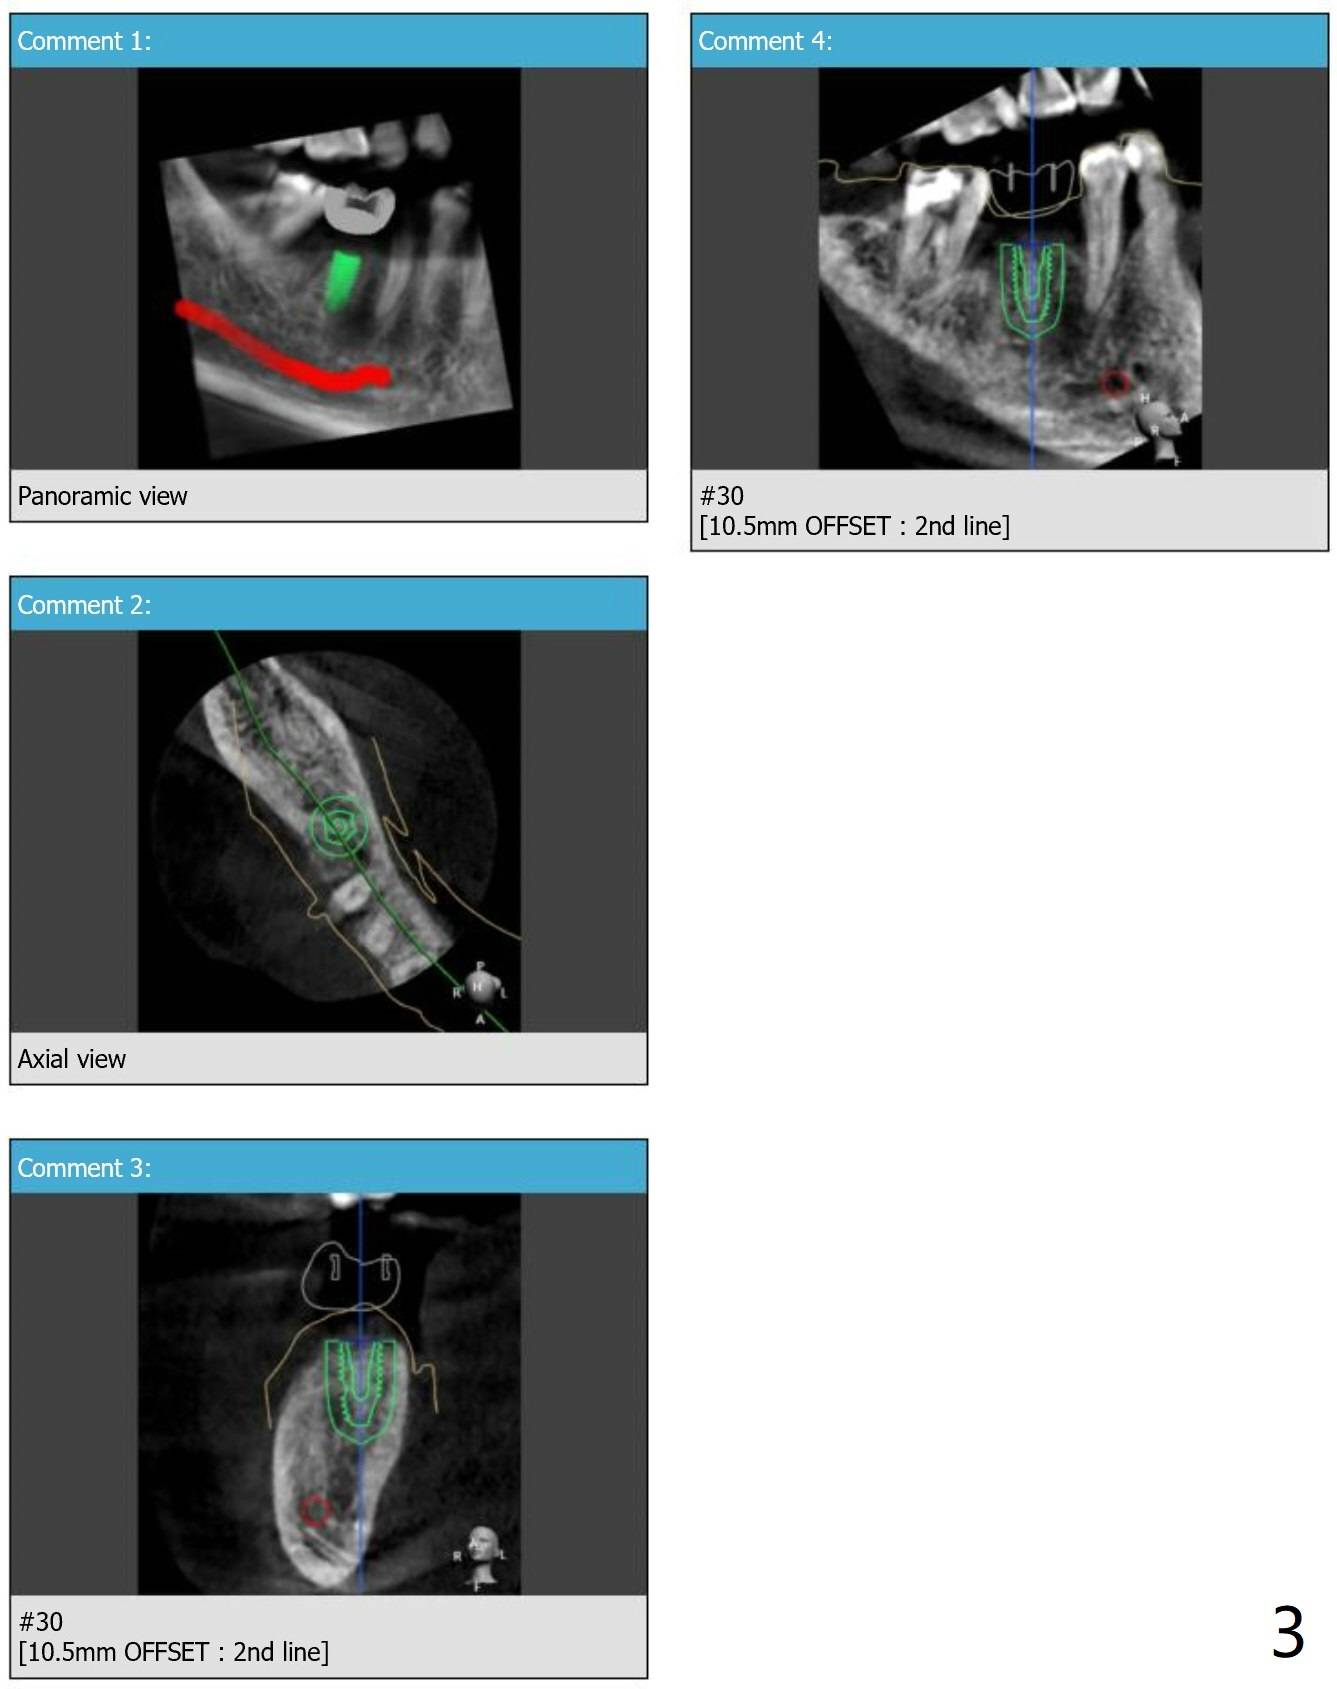

Guide Made Out of 5x5 cm Scan

Three months post socket preservation, the 60-year-od male patient returns for guided surgery at #30. Since the guide is made out of 5x5 cm CT scan, it may be not stable. Also do not expect high torque. Use cortical tap cautiously.